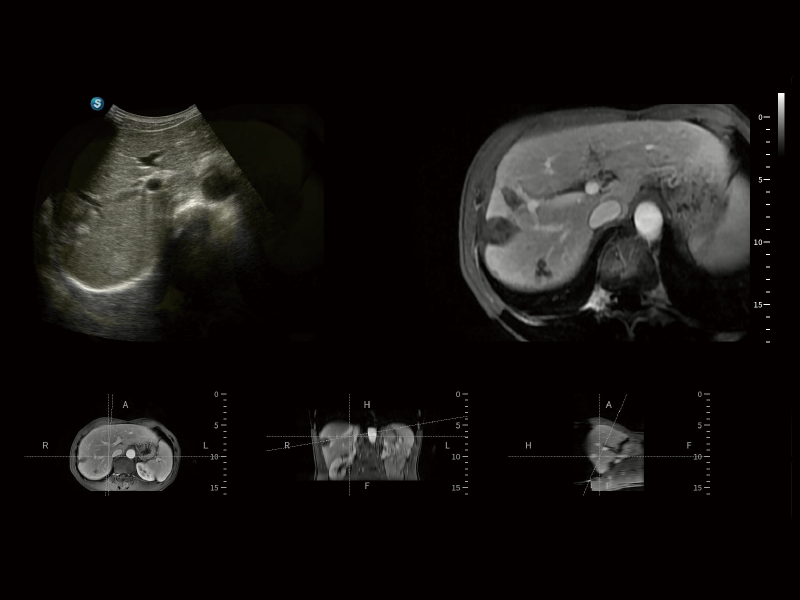

作為開立醫(yī)療全新打造的超高端旗艦超聲產(chǎn)品,從探頭抬起喚醒開啟掃查到多維探頭發(fā)射接收,通過先進(jìn)的場(chǎng)成像發(fā)射、自適應(yīng)聚合重建等技術(shù),基于RF Data原始射頻數(shù)據(jù)在圖像生成、高端功能等方面實(shí)現(xiàn)突破,提供多科室綜合臨床解決方案。

S80 提供多樣化超聲成像技術(shù),可滿足不同科室的需求,在助力掃查診斷和介入治療中發(fā)揮著重要作用。